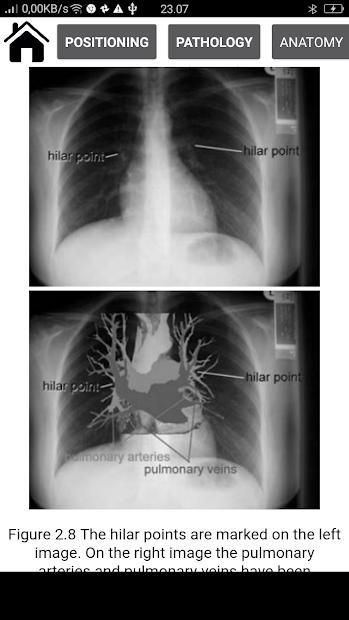

Radiographic Anatomy and Interpretation of the Chest and the Pulmonary System